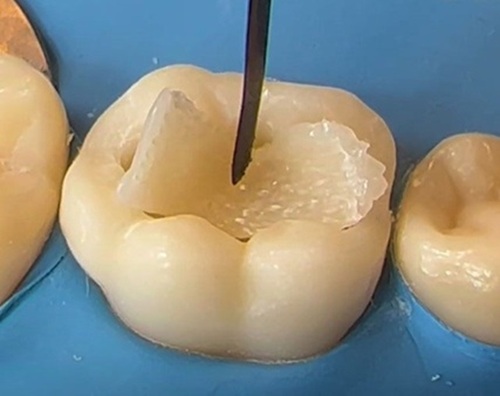

The key to Ribbond’s success (and what distinguishes Ribbond from the other fiber reinforcements) is its patented leno weave. Designed with a lock-stitch feature that effectively transfers forces throughout the weave without stress transfer back into the resin, Ribbond’s weave also provides excellent manageability characteristics.

Having virtually no memory, Ribbond adapts to the contours of the teeth and dental arch. For example; when making a periodontal splint, Ribbond tucks in interproximally without rebounding. In addition, unlike loosely braided or bundles of unidirectional fibers, Ribbond does not spread or fall apart when manipulated.

Since fiber reinforced resin structures derive their strength primarily from making laminates, high manageability and lack of memory is essential for close and accurate layering of the fibers. Inaccurate fiber placement results in voids or excessive composite on the tensile side of the fibers that will be prone to fracturing.

Ribbond bonds to any composite system. You choose the composite Magnified 110,000 time, SEM’s demonstrate complete incorporation of the resin to Ribbond’s fibers (note lack of voids). Forces within the resin are easily transferred to the fibers insuring that the Ribbond is an integral strength member of the prostheses.